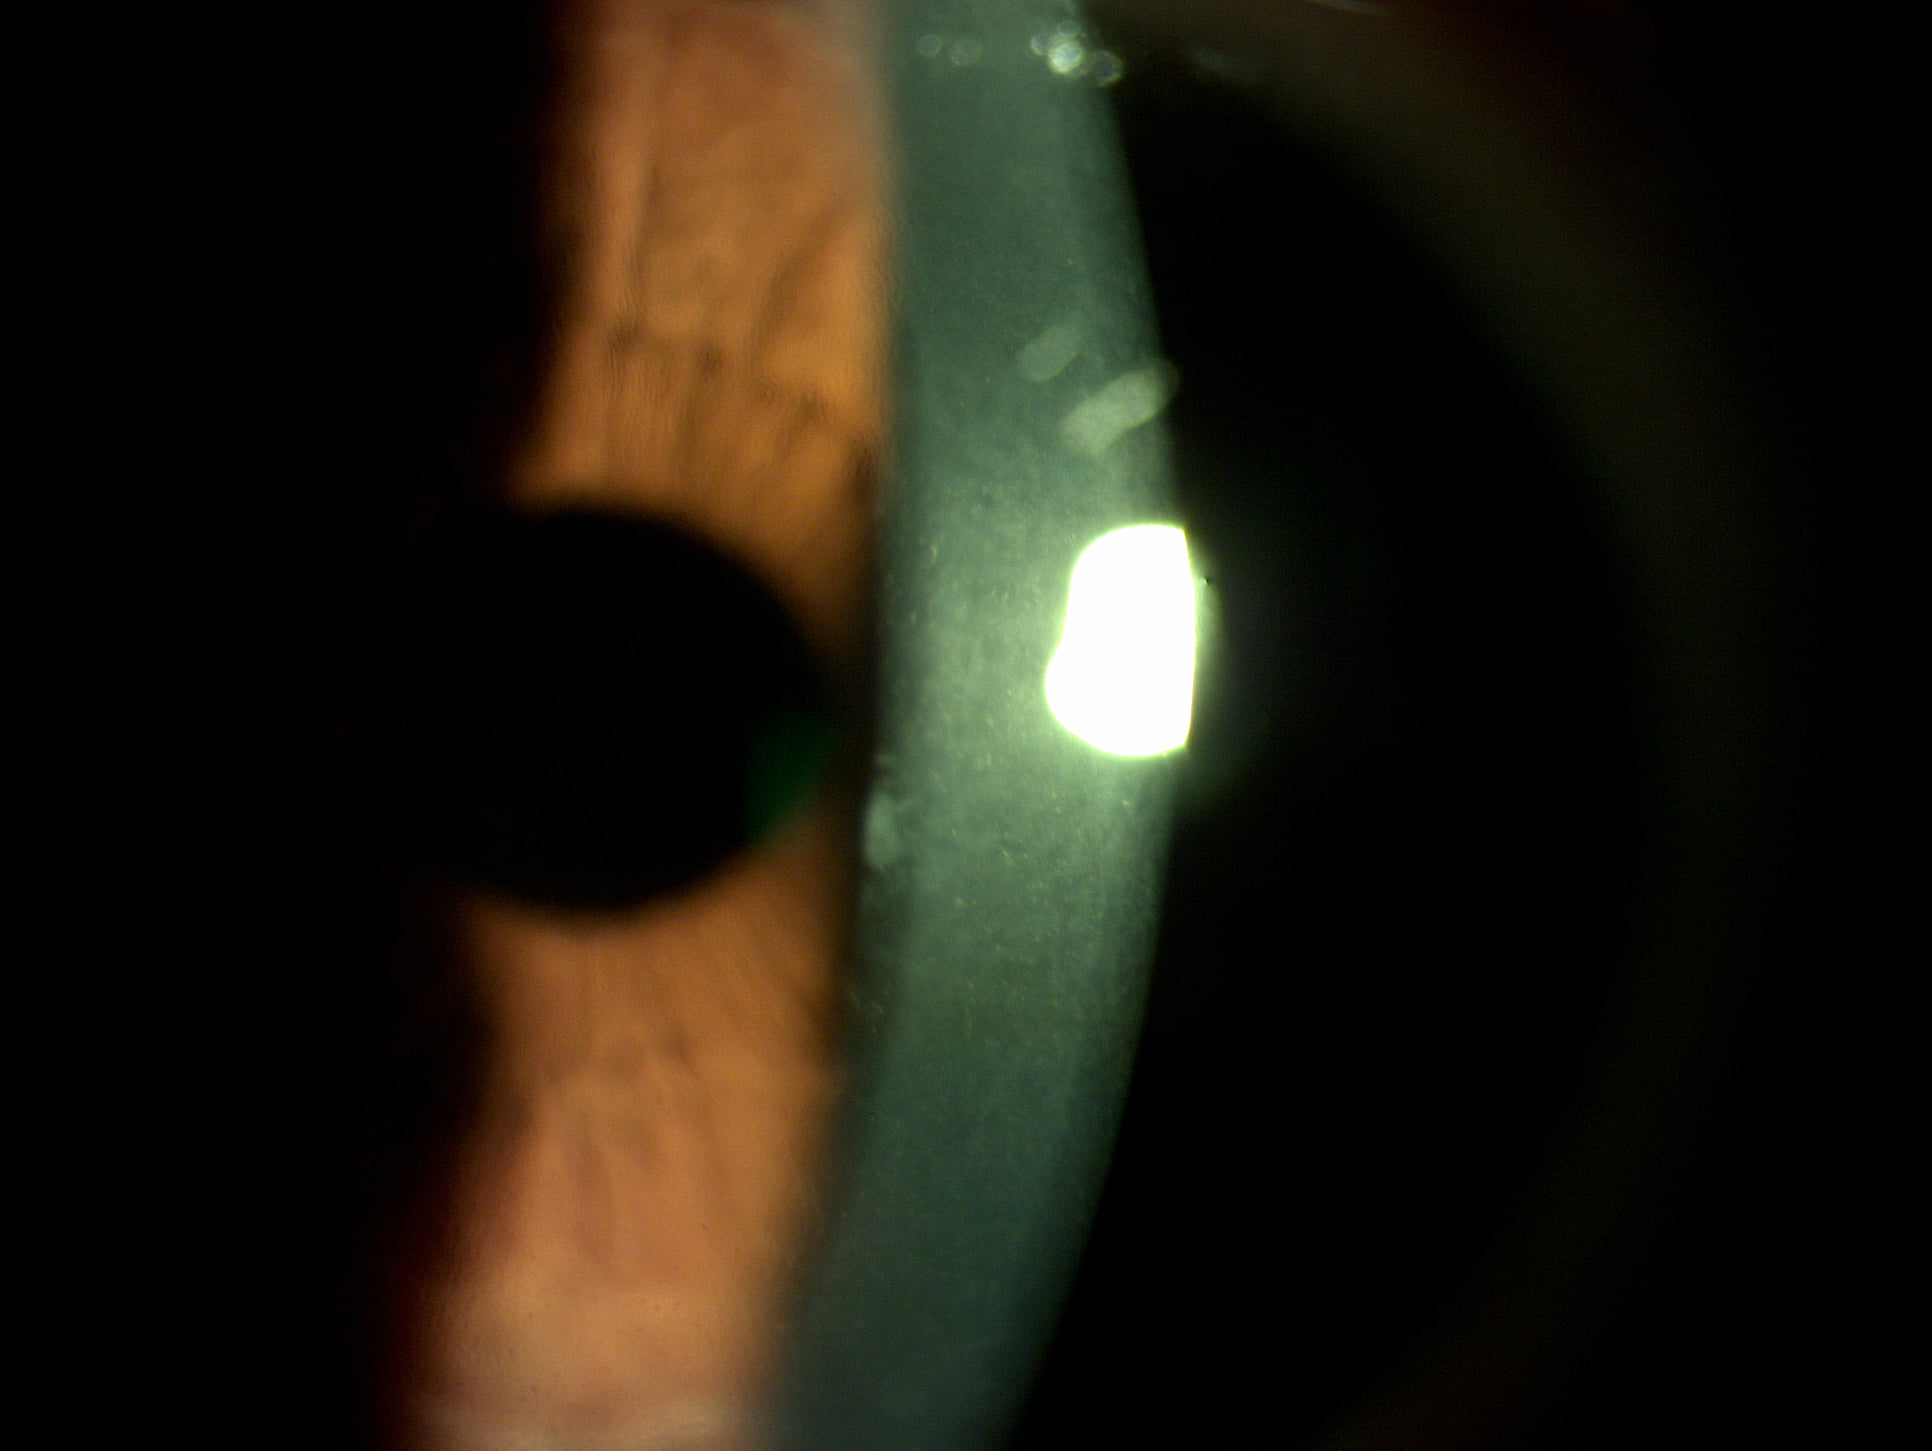

Mai jos, fotografii ale mai multor pacienti de-ai nostri cu Corneea Guttatta în faze medii, sau chiar avansate, la care am efectuat doar operația de cataractă, în urma căreia corneea a „supraviețuit” cu brio și nu a mai fost nevoie – cel puțin până acum – de un trasplant de cornee.